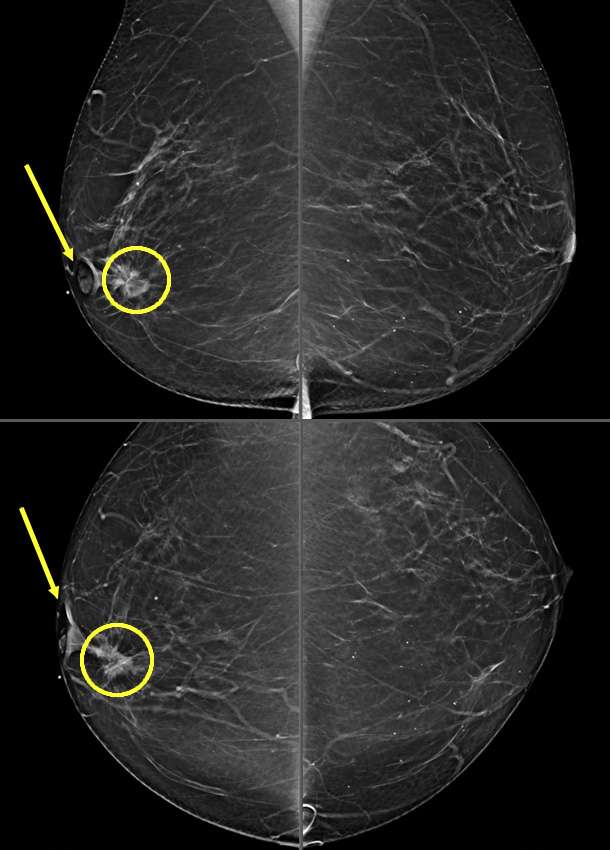

Figure 1: Skin Retraction on Mammogram. Patient presented for a palpable lump in the left breast. Mammographic MLO and CC projections demonstrate an irregular spiculated mass with associated architectural distortion (circle), and overlying skin retraction (arrows) in the upper outer quadrant of the left breast. Right side is included for comparison.